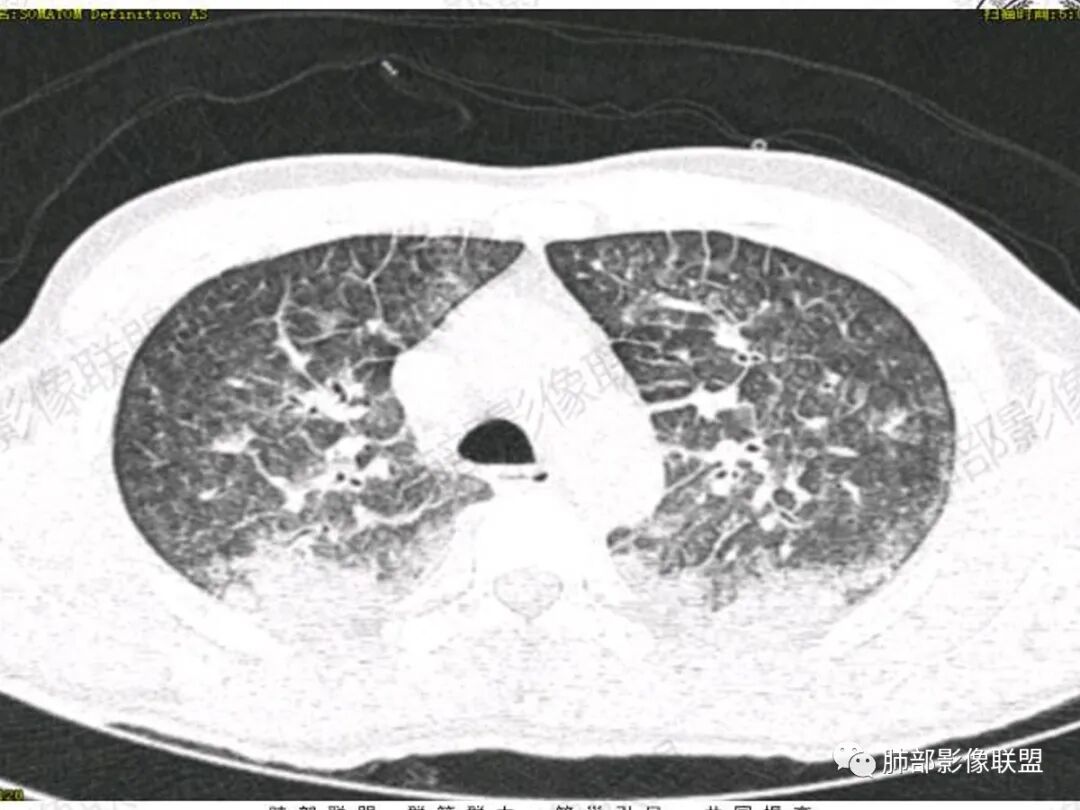

双肺上叶,下叶背段多发斑片状实变影,以胸膜下分布为主,部分重力作用,以背侧为主,部分小叶间质增厚,部分周围伴有散在磨玻璃影,边界欠清,临床急性病程,血象增及PCT明显增高,意识模糊,考虑:吸入性肺炎?鉴别:AHP?CEP?PCP

37岁男性 气促 两肺对称分布磨玻璃及小叶间隔增厚,两肺上叶后段及下叶背段为著,有重力分布,下部密度较高,请结合病史排查肺水肿,理化性肺泡损伤

双肺叶透亮度对称性减低,呈磨砂状,小叶间隔规则增厚,上叶为甚,左右肺叶中轴间质增厚(示淋巴回流障碍),双肺叶弥散磨GGO征,以肺腺泡分布,双肺上,下叶融合片状,有重力分布特点,心脏大,肺动脉干增粗,首选心源性肺水肿,但无胸腔积液。与急性肺损伤和ARDS鉴别

影像:两肺上叶小叶间隔增厚,斑片,腺泡结节,重力分布,下肺不累及

青年男性,气促7小时入院,意识模糊,白细胞及中性粒明显增高,PCT增高,CRP不高,心率快,体温正常,血压正常。胸部CT:双肺上叶小叶间隔光滑增厚,中轴间质增厚,弥漫性磨玻璃、多发斑片影,以上肺、背侧分布为主。影像表现考虑为肺水肿。病因:病史不支持肾功能衰竭、心源性、高原性肺水肿,无发热,似乎也不支持细菌、病毒、真菌等感染引起。吸入毒物?吸入水?

对称性小叶间隔增厚

高密度影重力趋势

病灶的分布以上肺为主

确实要考虑吸入,倾向于吸入的是气体类的可能,因为朝上走